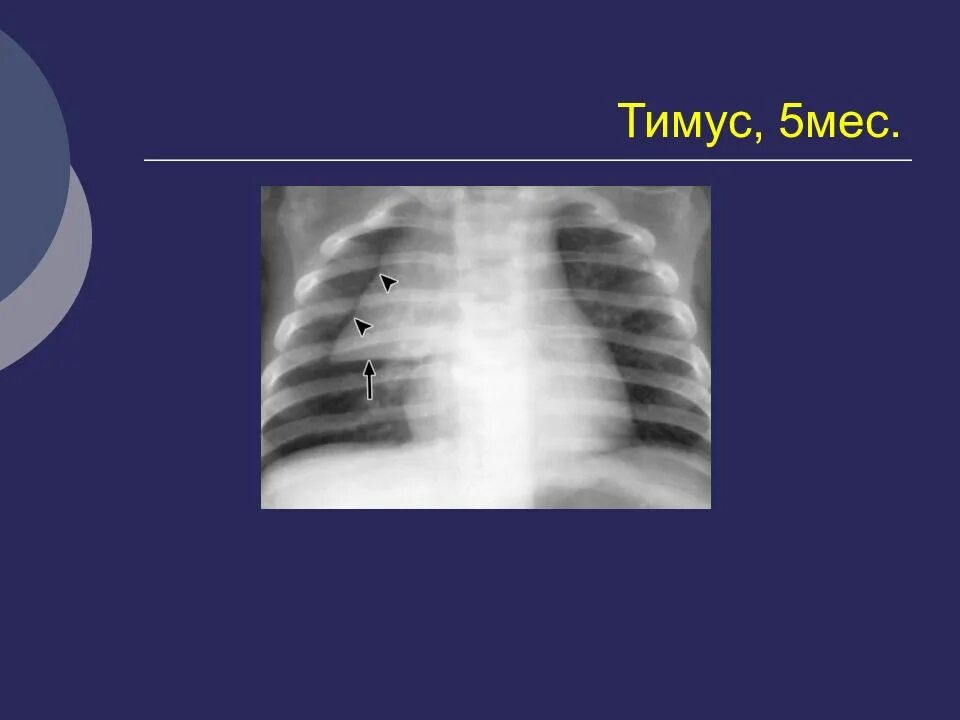

Метастазы в средостении легких